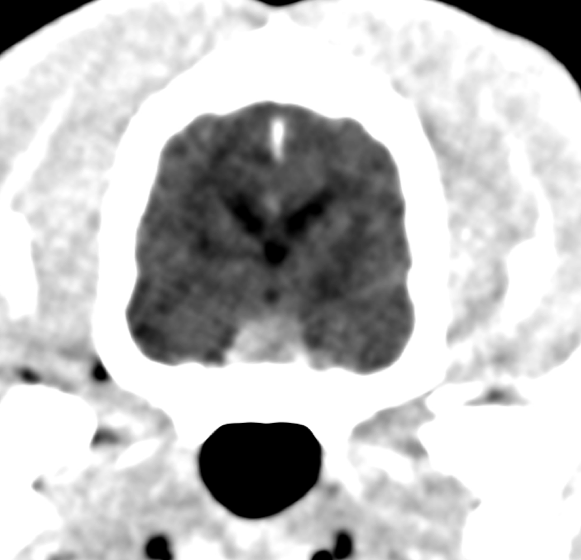

Afin de déterminer la forme d’hyperadrénocorticisme (hypophysaire ou surrénalienne), un examen tomodensitométrique de l'encéphale et de l’abdomen sont réalisés. Ces examens révèlent un macroadénome hypophysaire ainsi qu’une hypertrophie bilatérale des glandes surrénales (images 1a et 1b). Un dosage de l’ACTH endogène élevé vient confirmer le caractère sécrétant de cette masse pituitaire à l’origine de la maladie de Cushing du patient.

Images 1a & 1b : Image 1a (gauche) = Coupe transverse tomodensitométrique de l’encéphale, post-injection d’iohexol, montrant une masse pituitaire de 7,5mm d’épaisseur. Image 1b (droite) = Coupe transverse tomodensitométrique de l’abdomen montrant une augmentation de taille des surrénales bilatéralement.